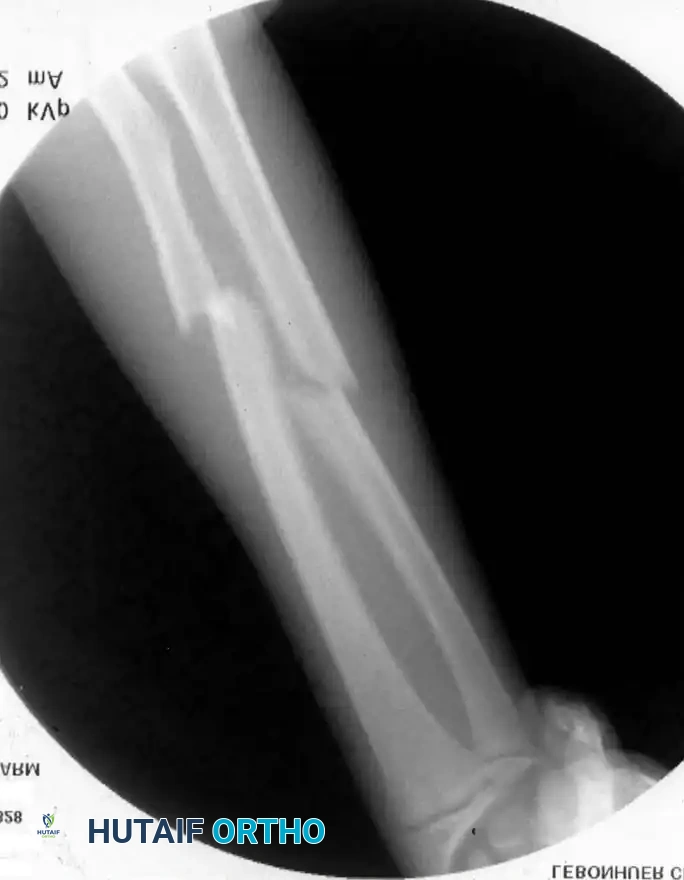

2. Elastic Stable Intramedullary Nailing (ESIN)

ESIN has become the gold standard for displaced, unstable pediatric forearm fractures. Lascombes et al. and Flynn and Waters popularized this technique, citing minimal soft-tissue dissection, preservation of the fracture hematoma, and the ability to achieve three-point biomechanical fixation.

Preoperative Planning:

Nail diameter should be approximately 40% of the narrowest intramedullary canal diameter. Titanium elastic nails (TENs) are preferred for their modulus of elasticity.

Step-by-Step Surgical Technique:

1. Positioning: The patient is placed supine with the arm extended on a radiolucent hand table. Fluoroscopy is positioned perpendicular to the arm.

2. Ulnar Nailing:

* An incision is made over the lateral aspect of the proximal ulna, 1-2 cm distal to the olecranon apophysis.

* The cortex is breached with an awl or drill.

* The pre-bent nail (contoured to create a bow that will tension against the inner cortices) is advanced antegrade down the ulnar shaft to the fracture site.

3. Radial Nailing:

* An incision is made laterally over the distal radius metaphysis, carefully avoiding the superficial branch of the radial nerve and the physis.

* The entry point is created, and the pre-bent nail is advanced retrograde.

4. Fracture Reduction and Nail Passage:

* Closed reduction is performed. The nails are advanced across the fracture sites under fluoroscopic guidance.

* If closed reduction is impossible due to interposition (often seen when initial translation exceeds 100%), a mini-open incision (1-2 cm) is made directly over the fracture to clear the soft tissue.

5. Final Seating: The nails are advanced to the opposite metaphyses. The trailing ends are cut, leaving 1-2 cm outside the bone but buried beneath the skin to facilitate future removal.